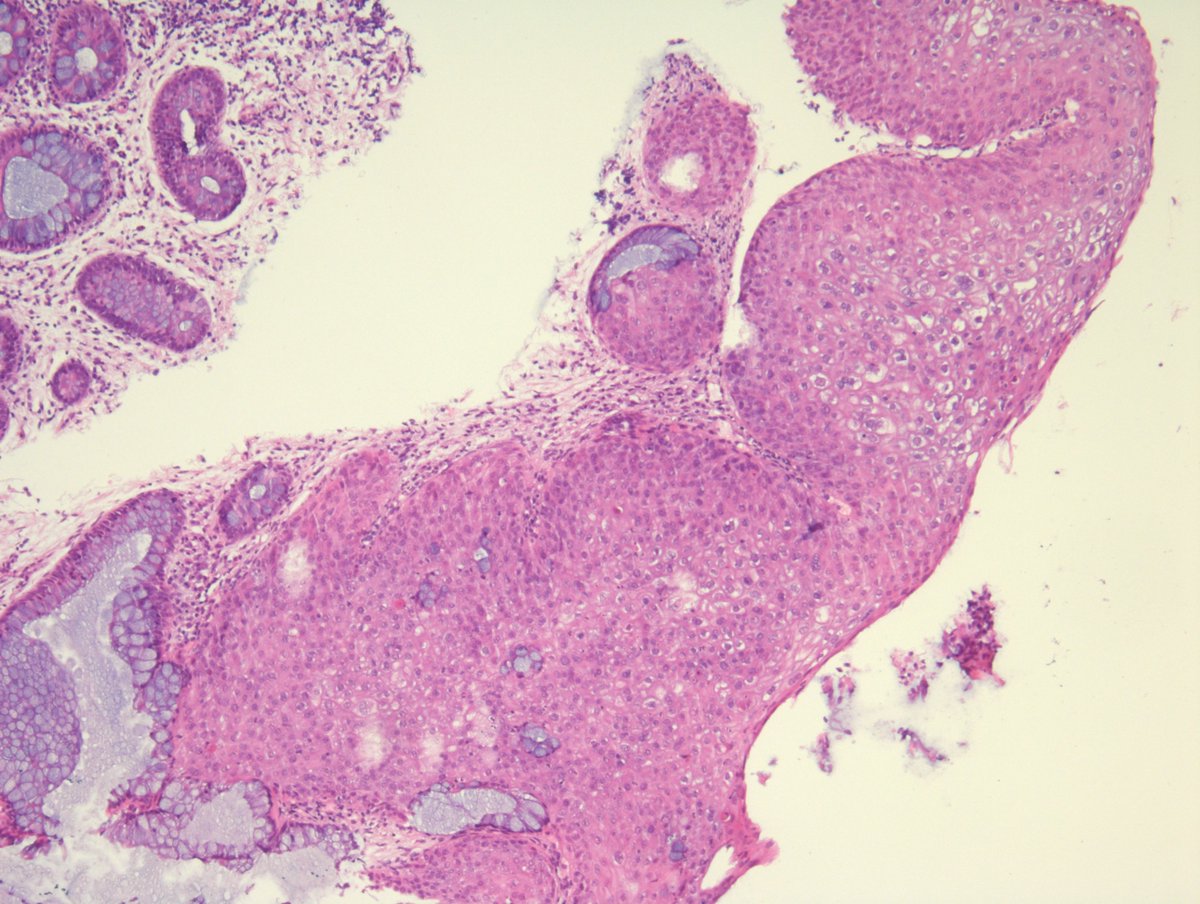

#GUpath external re-review🔬of penile lesion in a patient with a h/o penile cancer at this site (s/p partial resection a year back) recurrent cancer? dysplasia? negative for malignancy? #pathresidents: what say you?🤔

slusagar's tweet image. #GUpath external re-review🔬of penile lesion in a patient with a h/o penile cancer at this site (s/p partial resection a year back)

recurrent cancer?  dysplasia? negative for malignancy?

#pathresidents:  what say you?🤔